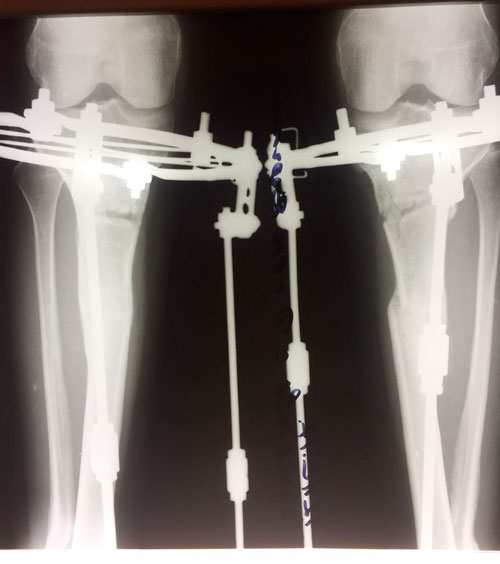

Исходник - 47 лет. Россия. Дагестан.

Переделка после не удачной операции в Дагестане.

Дата операции 12.10.2017г.

Дата снятия аппаратов 26.01.2018г.

Срок лечения 103 дня.